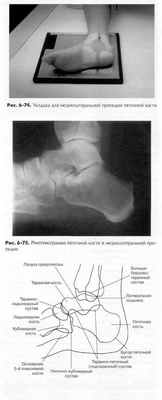

БОКОВАЯ - МЕДИОЛАТЕРАЛЬНАЯ ПРОЕКЦИЯ: ПЯТОЧНАЯ КОСТЬ

Пациент лежит горизонтально на боку, изучаемой стороной вниз. Положите пациенту подушку под голову. Колено изучаемой ноги должно быть согнуто под углом 45°, другая нога служит опорой.

Укладка снимаемой области Щ

• Пяточная кость должна быть расположена в центре снимка

(рис. 6-74).

• Под колено изучаемой ноги следует положить подушку (сло

женное полотенце) так, чтобы подошвенная поверхность

была перпендикулярна плоскости кассеты.

• Голеностопный сустав и ступня должны быть в истинно бо

ковой укладке, которая помещает латеральную лодыжку при

мерно на 1 см кзади от медиальной лодыжки.

• Стопа должны быть согнута в тыльном направлении так,

чтобы она находилась под прямым углом к голени.

Центральный луч

• ЦЛ перпендикуляренкассете и направлен на точку на 2,5 см

внутрь от медиальной лодыжки.

• Минимальное РИП составляет 100 см.

Критерии оценки рентгенограммы Видимые анатомические структуры.• Должна быть изображена вся пяточная кость в профиль с таранной костью и дис-тальным отделом голеностопного сустава сверху, ладьевидной костью и открытой рентгеновской суставной щелью между пяточной и кубовидной костью дистально. Укладка.• Отсутствие ротацииподтверждается наложением передних частей таранной кости, открытым таранно-пяточ-ным суставом и латеральной лодыжкой, накладывающейся на заднюю часть (половину) большеберцовой и таранной кости. Пазуха предплюсны и пяточно-кубовидный сустав должны выглядеть открытыми.

Диафрагмирование и ЦЛ.• ЦЛ и центр снимка должны быть на 2,5 см дистальнее верхушки латеральной лодыжки, как ее видно через таранную кость. • Область диафрагмирования должна включать часть голеностопного сустава и таранно-ладь-евидный сустав, а также основание пятой плюсневой кости. Параметры экспозиции.• Оптимальная экспозиция поможет визуализировать некоторые мягкие ткани и более плотные части пяточной и таранной костей. Контуры части малоберцовой кости должны быть едва видны через таранную кость. Отсутствие движения во время экспозиции дает четкую трабеку-лярную структуру кости.

Рис. 6-76.Анатомическая схема пяточной кости в медиолатеральной проекции

Диафрагмирование.С четырех сторон максимально близко к области пяточной кости, включив дистальный отдел голеностопного сустава.